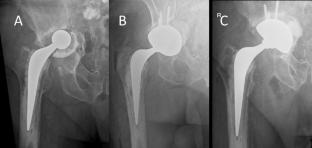

A single-centre prospective cohort study of 101 aseptic rTHA in 100 patients was undertaken. Inclusion criteria were patients suitable for the use of the uncemented acetabular component, aged 18–95 years, willing and able to comply with the study protocol, and provide informed consent. Those with inadequate bone stock to support fixation of the prosthesis were excluded. Functional assessments included the Oxford hip score, Forgotten joint score, EQ-5D, EQ-VAS, pain VAS and satisfaction. Radiographic assessment included acetabular lucent lines and lysis according to Delee and Charnley zones and loosening.

The mean age was 72.5 (standard deviation 11.6) and consisted of 54 females and 46 males. Mean follow-up was 3.1 (range 2 to 4.9) years during which 10 patients died. Indication for rTHA included: loosening of the acetabulum (n = 82), instability (n = 11), broken femoral stem (n = 3), metal on metal with pain and pseudotumour (n = 2), pain (n = 2) and loosening of femoral component (n = 1). There were two re-revisions for deep infection. This resulted in a 1-year all-cause survival of 99.0% (95% CI 97.1 to 100) and 4-year survival of 96.2% (95% CI 90.5 to 100). There was only one case with lucent lines in all three zones and had not osseointegrated, but the component remained stable at 3-years follow-up. All PROMs demonstrated a clinically meaningful improvement, which was significant (p < 0.001) at both 1- and 2-years. Patient satisfaction with their revision THA was 85.6% and 85.3% at 1- and 2-years.